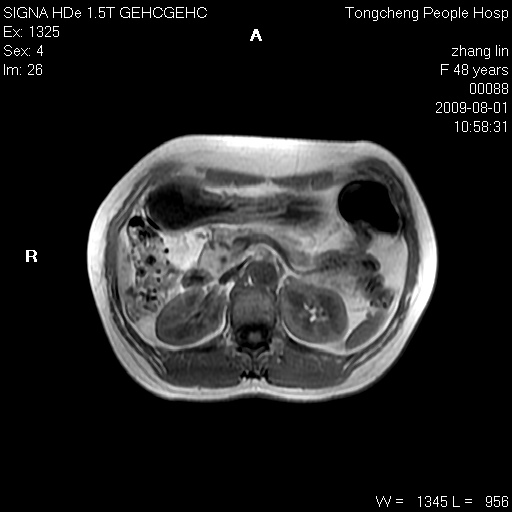

女,48岁。健康体检,彩超发现右肾占位性病变。平素健康。

临床诊断:右肾占位性病变,性质待定(囊肿?肿瘤?)。

上中腹部mr平扫+增强扫描,图像如下:

右肾上极见一类圆形病灶,t1wi呈等信号t2wi呈等高混杂信号,三期增强无强化,边界清---考虑囊肿出血。